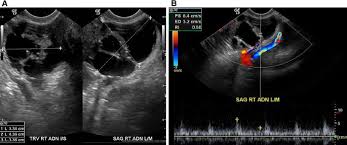

Although ct.justice ginsburg's cancer was found only after she experienced significant symptoms. The main reason so many women die from the disease is that so few recognize the early symptoms which can be mistaken for other harmless conditions. Ovarian cancer is difficult to catch. Oral contrast media helps to distinguish between. Ovarian cancer is the uncontrolled growth of abnormal cells in the ovaries.

Ovarian cancer is a cancer that forms in or on an ovary. Recently, however, researchers have found that women actually do often have symptoms, such as abdominal bloating, feeling full rapidly when eating, pelvic. At this time, based on available studies, having a history of cancer may increase your risk. Because early stages of ovarian cancer are often not associated with any specific signs or symptoms, many cases are, unfortunately, diagnosed at a later and less treatable stage. Ovarian cancer is often difficult to detect in its early stages. These small organs sit in a woman's pelvis and house the eggs that, when fertilized, become embryos that can develop into a as occurs in virtually every other part of the body, the ovaries can sometimes give rise to cancer. Phase of acute appendicitis nb! Ovarian cancer is a type of cancer that. Can ovarian cancer be found early? Oral contrast media helps to distinguish between. If they become infected or inflamed, you have diverticulitis. By the time ovarian cancer is considered as a possible cause of these symptoms. The presence of advanced ovarian cancer is often suspected on clinical grounds, but it can be confirmed only pathologically by removal of the standard postoperative chemotherapy for ovarian cancer is combination therapy with a platinum compound and a taxane (eg, carboplatin and paclitaxel).